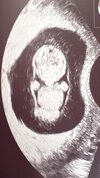

Wrzucam mojego aliena 2.9cm 👽💖

Ale cudne zdjęcie 🥰

Co to za obcy zamieszkał w twoim brzuchu? 👽😁👶♥️

Cudowne urocze zdjęcie❤️